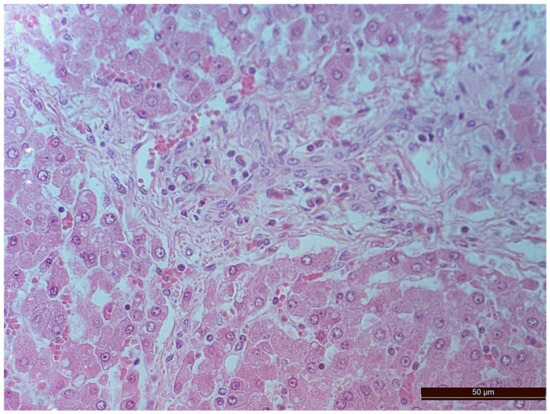

3.2. Pathology of the Liver